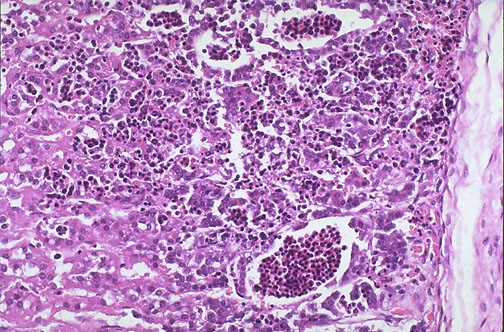

Expansion of erythropoiesis in the fetus with a congenital hemoglobinopathy, in this case alpha thalassemia major, has led to marked extramedullary hematopoiesis. There are numerous RBC precursors in the fetal adrenal gland seen here.